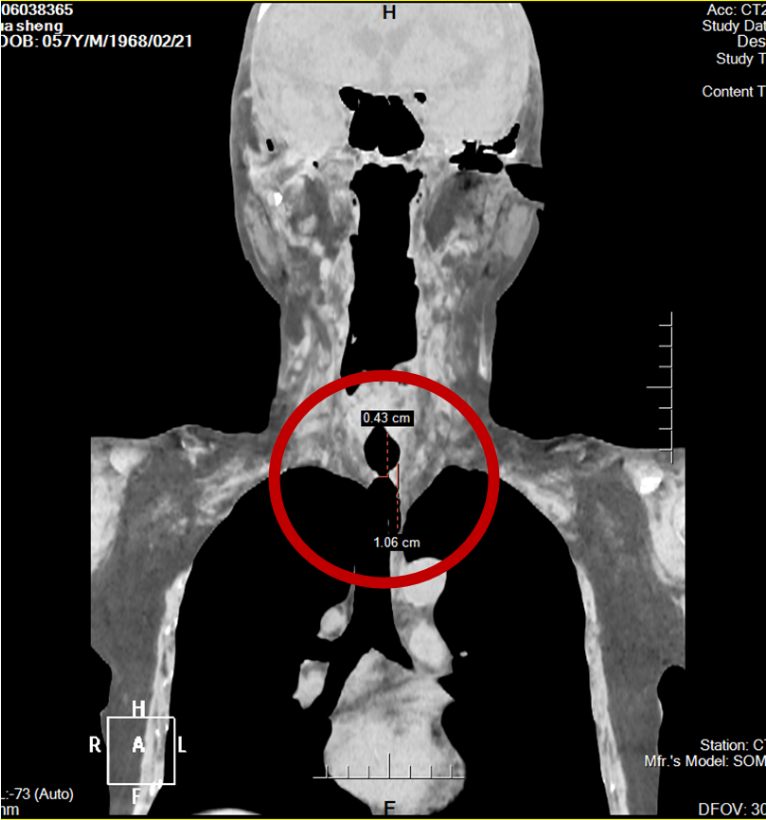

术前CT测量

该患者为57岁男性,因既往气管插管史,反复出现呼吸困难伴晕厥,因手术难度高、风险大,最终求助于昆医大附二院。检查显示,患者距声门3cm处气管仅4mm宽(正常成人男性18-20mm),极重度狭窄,随时可能窒息,病情危急。昆医大附二院呼吸介入团队即刻启动多学科会诊,柴燕玲主任带领团队,联合麻醉手术科等多方反复评估风险、敲定治疗方案。

根据狭窄严重程度,可分为四级:轻度狭窄(管腔直径减少<30%)、中度狭窄(管腔直径减少30%-50%)、重度狭窄(管腔直径减少50%-70%)、极重度狭窄(管腔直径减少>70%)。该患者气管管腔仅4mm,仅为正常成年男性气管直径(18-20mm)的22%,属于极重度狭窄,系急危重症,一旦出现痰栓、水肿或痉挛,极易导致管腔完全闭塞、患者窒息死亡,需紧急开放气道。